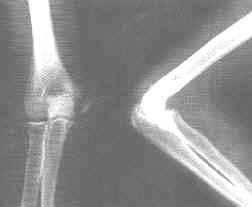

肱骨內上髁骨骺與肱骨下端內髁部分離、移位或鏇轉移位,並據骨折片移位情況判斷其移位程度。兒童肱骨內上髁骨折,較易與肱骨內髁、橈骨小頭撕脫骨折有移位者相混淆,兒童肱骨內髁骨骺尚未出現之前(通常6歲),骨化中心的徵象不能在X線片顯示出來,骨骺線未閉合,更增加了鑑別診斷難度,必要時拍對側肘關節X線片。詳細體格檢查,詢問受傷情況,結合年齡特點。只有這樣,才能準確診斷並選用較好的手術治療方法。

X線診斷十分重要,應注意仔細觀察。

Ⅲ、Ⅳ度骨折應注意觀察內上髁骨骺是否存在,如有困難應強調拍攝雙側同位置的正側位或斜位X線片,觀察雙側關節間隙是否等寬,雙側內上髁是否對稱。5歲以下的兒童,因肱骨內上髁的骨化中心尚未出現,故較難與肱骨內髁骨折區別。嚴重損傷時應注意有無合併橈骨頭、尺骨鷹嘴、肱骨外上髁骨折存在。